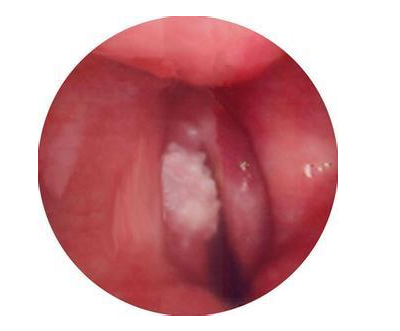

声带白斑

声带白斑是喉白斑的一种,喉白斑主要发生在声带,其它部位白斑很少见。

声带白斑是指声带粘膜表面有白色斑块状物。病理称之为角化症,因为白斑存在过度角化和角化不全。

正常声带表面没有角质层,如出现角质层,称之为过度角化。

如果角质层内没有残余细胞核,称之为角化;如果角质层有细胞核残余,称之为角化不全。

声带白斑都存在过度角化、角化不全。